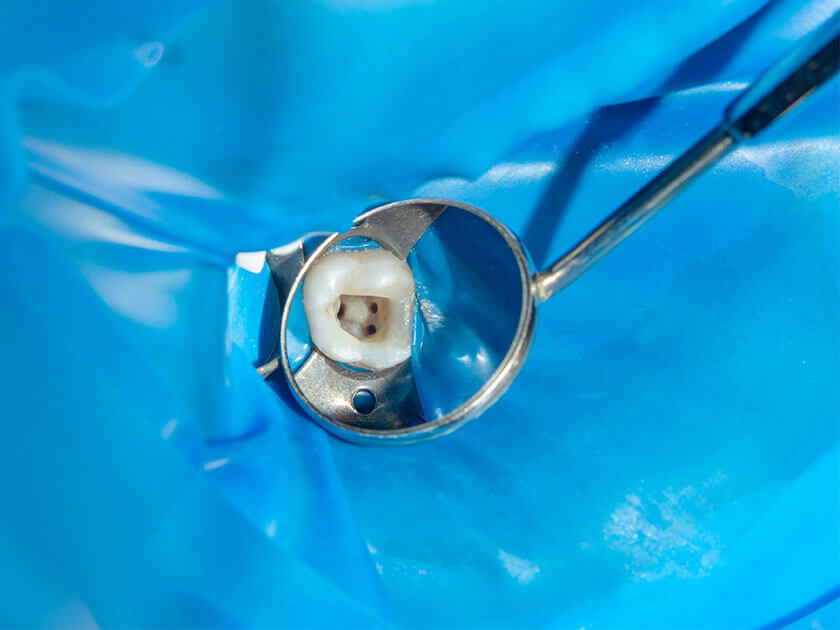

顎骨に人工歯根を埋め込む外科処置が必要なインプラント治療には、精密な診断・手術が求められます。また手術が成功しても、土台となる歯周組織や顎骨が健康でないとインプラントが安定せず、長期間の使用が困難です。

当院では歯周病専門医が事前に歯周の状態を確認し、歯周病の場合はその治療をしたうえでインプラント治療に進みます。

『徹底した院内感染対策』

より効果的なクラスBの滅菌器を導入し、治療に使う器具などは必ず滅菌処理して滅菌パックに入れて保管します。可能なものはディスポーザブル(使い捨て)にしています。

また、治療する歯だけを露出させるラバーダム防湿を行ない、患部が唾液や血液から細菌に感染しないようにしています。